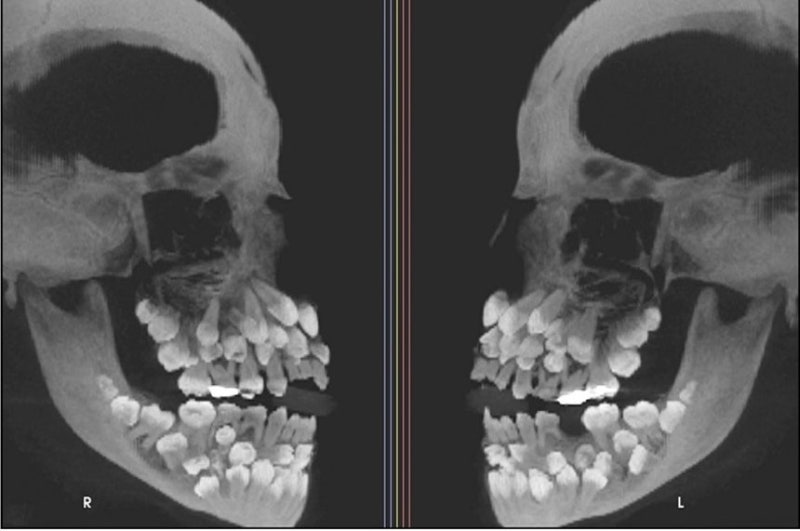

“32개가 정상인데”…11세 소녀 치아가 무려 81개, 학계 ‘발칵’

브라질 한 10대 소녀에게서 81개 치아가 발견됐다. [VN익스프레스] 11세 소녀 입 안에서 치아가 무려 81개나 발견돼 학계에 충격을 안겼다. 일반적인 치아 개수는 32개다. 최근 VN익스프레스 등 외신에 따르면